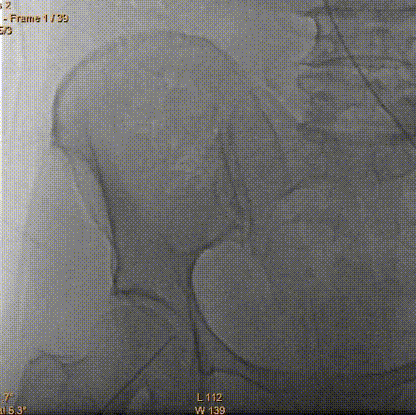

瓣膜释放2/3同时发现患者血压降低,立即释放冠脉支架

瓣膜脱钩

AV23瓣膜完全释放

术后无瓣周漏

平均压差降为9mmHg平均流速降为1.41m/s